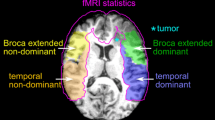

To minimize inter-subject variability, we calculated multiple LIs on fMRI maps through a threshold-independent method [32, 33]. The workflow was as follows: (1) 3D T1-weighted and functional images were registered to MNI152 standard space through nonlinear registration (ANTS). The registration of functional images was based on the first volume of the echo-planar sequence and applied to the correlation maps generated after post-processing. fMRI activation maps were overlayed on structural images before and after co-registration for quality assessment; (2) co-registered 3D T1-weighted images were parcellated according to the automated anatomical labeling—AAL atlas; (3) for every subject, we calculated the mean value of the 5% most-activated voxels on the correlation map; (4) we considered the number of voxels above 80% of this mean within each region of interest (ROI) and applied the traditional formula, LI = (L-R)/(L + R), where L and R represent the number of voxels in the left and right ROI, respectively.

We calculated five LIs corresponding to the following ROIs: hemispheric ROI, excluding cerebellum and visual cortex; temporal lobe; frontal lobe; BA, including the pars opercularis and triangularis of the inferior frontal gyrus; and WA, including the posterior aspect of the superior temporal gyrus. For each subject, an experienced neuroradiologist confirmed the findings by visually comparing the LIs generated by our method to the respective fMRI maps overlayed on 3dT1 anatomical images.